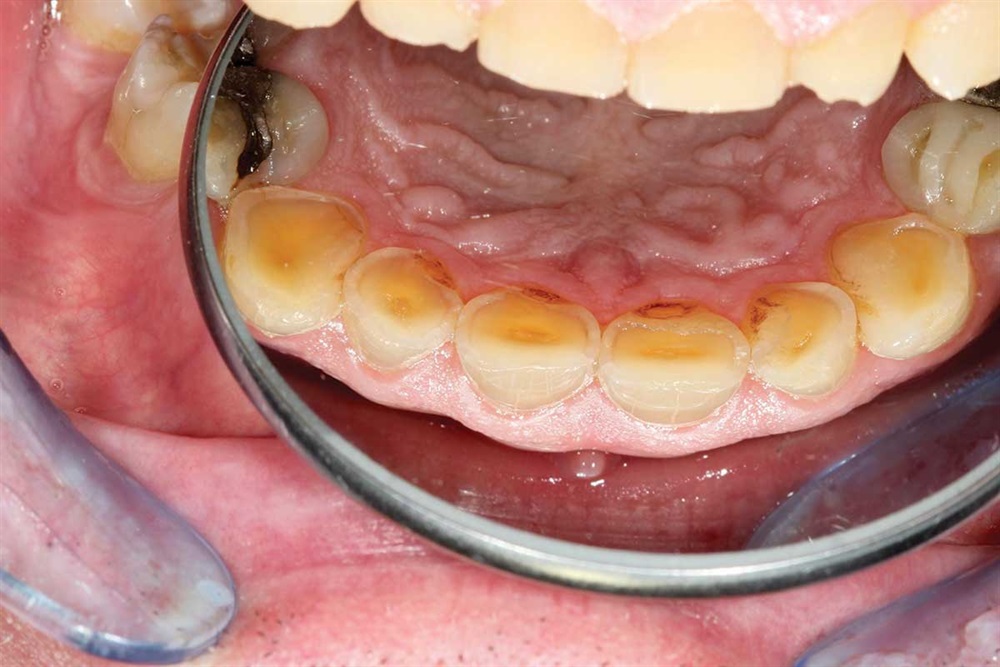

Fig. 1: June 2018. Where did all the tooth structure go? Grinding in protrusion? There is serious wear and tear. This 63-year-old gentleman has been wearing out his teeth, especially in the past 10 years.

Fig. 2: Maxillary teeth.